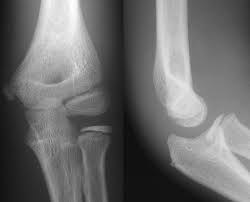

10+ Elbow Anatomy Xray. Elbow injuries have characteristic appearances. This is an online quiz called elbow xray anatomy.

Soft tissue abnormality is often the only evidence of bone injury.